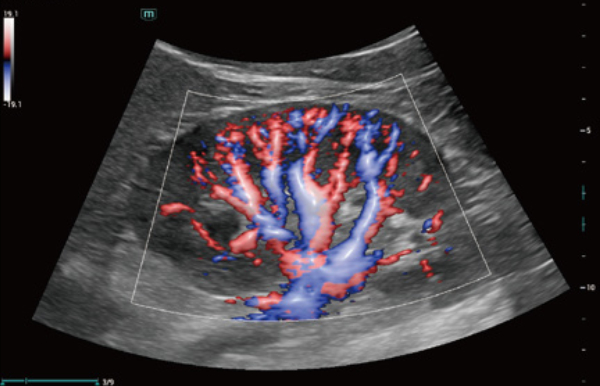

Comprehensive Imaging Solutions Powered by ZST+

The ZST+ platform is an extraordinary innovation, representing an ultrasound evolution. Transforming ultrasound metrics from conventional beam-forming to channel data based processing. It overcomes the traditional trade-off limitation among spatial resolution, temporal resolution and tissue uniformity, delivering exceptional image quality for infinite imaging solutions with non-stop improvements.